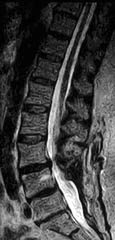

Cervical Spine |

|

Upright Neutral |

Upright Extension |

Unsuspected

Disc Herniation in Extension |

Lumbar Spine |

Recumbent, Weightless |

Upright, Weight-Bearing |